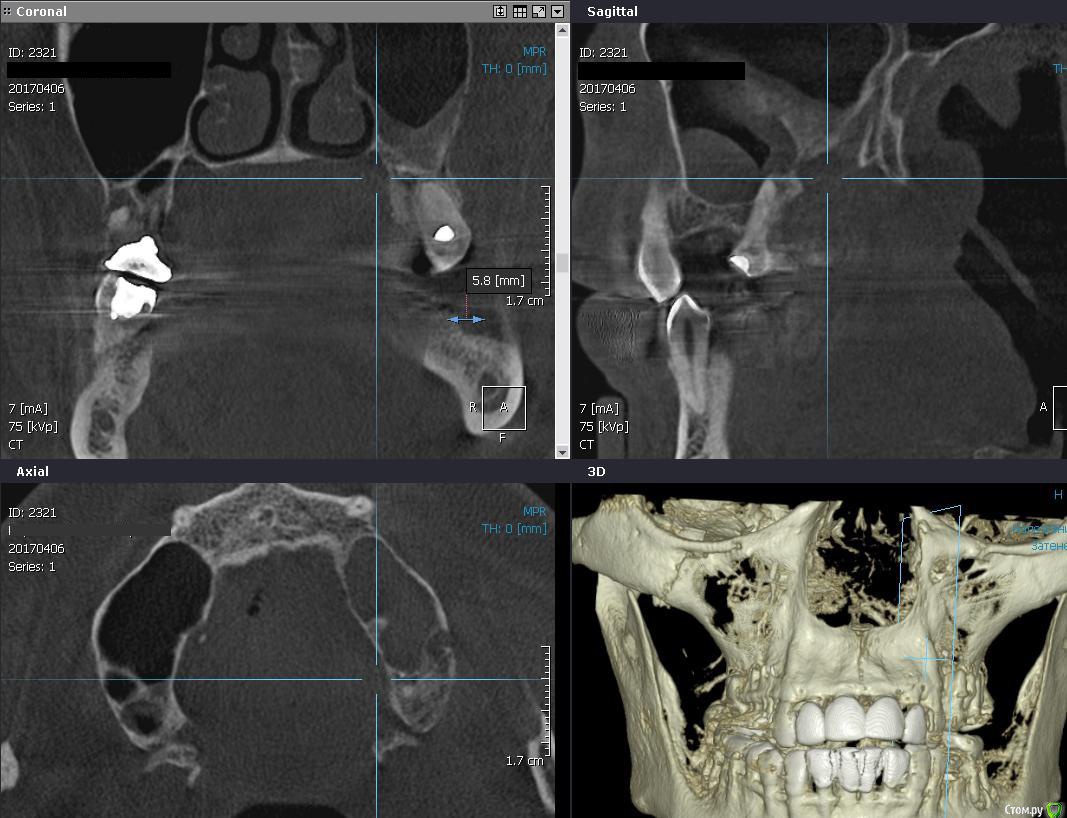

Romanson Опубликовано 10 апреля, 2017 Поделиться Опубликовано 10 апреля, 2017 Здравствуйте, подскажите как бы вы поступили в такой ситуации? Ничего не беспокоит, на затрудненное дыхание не жалуется.Удалить, отпустить, сделать повторное кт - если все нормально, то делать синуслифтинг, устанавливать имплантанты?Удалить, попытаться сделать пункцию мягкотканного компонента, если есть содержимое то пытаться вылущить оболочку из пазухи?Как действуете в подобных ситуациях? Ссылка на комментарий